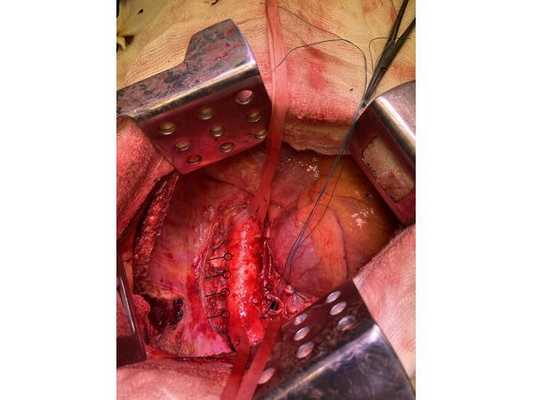

Интраоперационное фото: клипированные межрёберные артерии; аорта на тесёмочных держалках по краям зоны резекции адвентиции; культя главного бронха с провизорными швами при ушивании по Оверхольту

- боковая торакотомия (вскрытие грудной клетки) слева;

- пневмонэктомия с резекцией адвентиции (наружной оболочки) аорты, париетальной и медиастинальной плевры и мышечной стенки пищевода;

- медиастинальная лимфаденэктомия.

1. В положении на правом боку с раздельной вентиляцией лёгких выполнена боковая торакотомия слева. При ревизии:

Учитывая данные интраоперационной ревизии, диагноз скорректирован: центральный местно-распространённый немелкоклеточный рак нижней доли левого лёгкого с врастанием в адвентицию аорты и ткани средостения — cT4NxM0. Принято решение о выполнении пневмонэктомии (полного удаления лёгкого).

2. Выделены и взяты на держалки верхняя и нижняя лёгочные вены, выделен ствол лёгочной артерии, который также взят на держалку. Выполнено пробное пережатие лёгочной артерии — нарушений гемодинамики (движения крови по сосудам) и гемоксигенации (насыщения крови кислородом) нет.

3. Последовательно прошиты сшивающими аппаратами и пересечены нижняя и верхняя лёгочные вены и ствол лёгочной артерии. Выявлено, что опухоль подрастает к мышечной стенке пищевода, выполнена краевая резекция мышечной стенки пищевода на протяжении 2 см.

4. Острым путём отсечён левый главный бронх, при этом обнаружено, что опухоль распространяется перибронхиально. Культя левого главного бронха реампутирована (ампутирована повторно) в пределах визуально здоровой ткани стенки бронха, до 1,5-2 см от карины трахеи (гребня хряща между разделением двух главных бронхов). Центральная часть культи левого главного бронха ушита по Оверхольту.

5. Отступив по грудной стенке от края врастания опухоли в аорты на 2 см, рассечена и отсепарована (отделена хирургически) париетальная плевра и адвентиция аорты. Аорта мобилизована по типу "ручки чемодана" и взята на тесёмочные держалки выше и ниже места врастания опухоли.

6. Скелетизируя грудную стенку и аорту, с перевязкой левых межрёберных артерий, на участке рёбер 4, 5, 6 и 7 выполнена полуциркулярная резекция адвентиции аорты, мягких тканей грудной стенки с париетальной плеврой и тканей средостения.

7. Пневмонэктомия. Проверка аэростаза (герметичности) под уровнем жидкости — просачивания воздуха в области культи бронха нет.

8. Выполнена лимфодиссекция из области лёгочной связки, области бифуркации трахеи (места её разделения на главные бронхи), аортального окна, левого трахеобронхаильного угла и нижних паратрахеальных лимфатических узлов слева. Проверка гемостаза — сухо.

10. В плевральную полость заведён толстый силиконовый дренаж. Послойное ушивание раны, рёбра сведены тремя перикостальными швами. Наложена асептическая повязка.